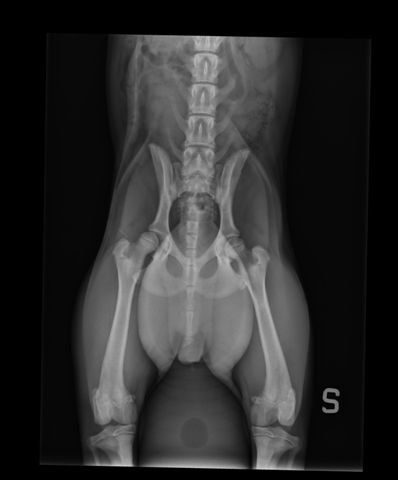

Presso la nostra clinica, la prevenzione della displasia delle anche inizia con uno studio radiografico approfondito, effettuato in anestesia o sedazione controllata. L’esame è sicuro e permette di valutare l’articolazione anche nei cuccioli, già a partire dai 3 mesi e mezzo di età.

- radiografie in più proiezioni (standard, distratta, a rana e DAR);

- valutazione della colonna e, se necessario, anche dei gomiti.